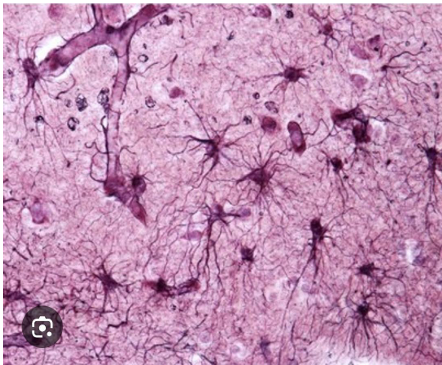

Astrocytes

Support – they hold neurons together forming a framework in the brain

○ Nutrition – they act as a bridge between neurons and blood vessels helping absorb nutrients.

processes

Ano tawag sa mga galamay ng astrocytes

Near Capillaries

Saan nahahanap ang astrocytes

Astrocyte

Long and Thin processes